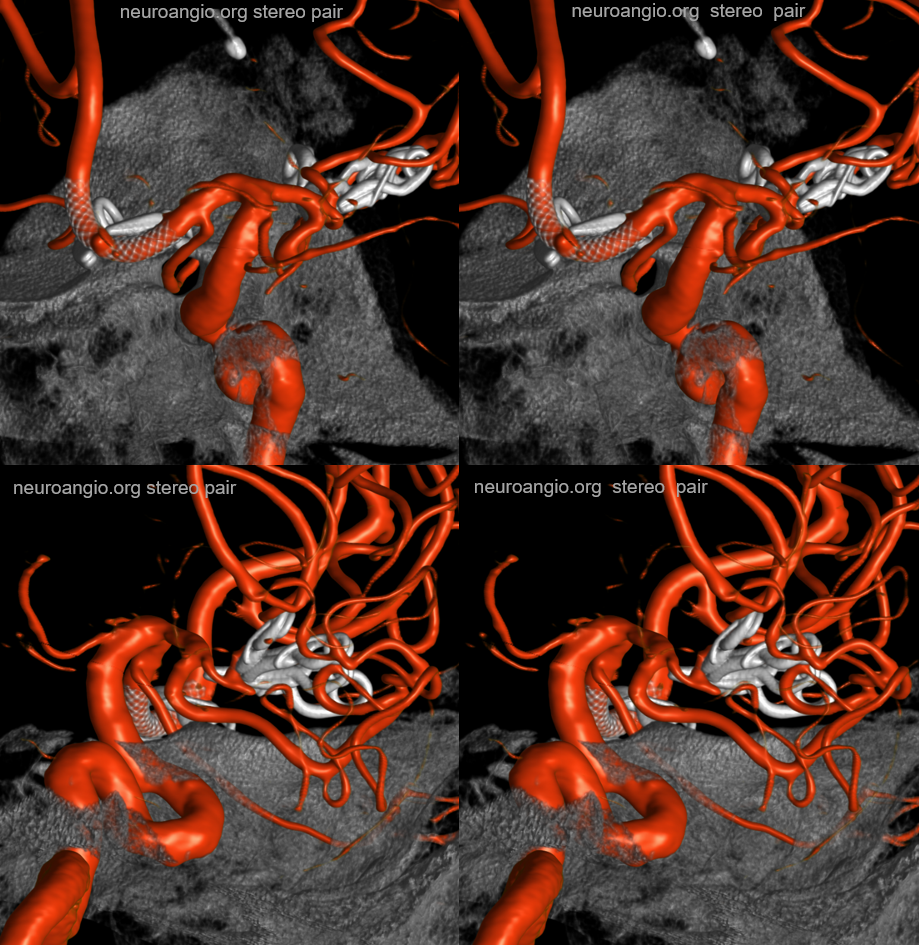

Patent Superior Hypophyseal artery (arrow) post Pipeline Embolization Device placement (6 months post).

The patency of jailed vessels post technically optimal flow diversion (good wall apposition, good antiplatelet coverage) is principally determined by the collateral potential of the jailed artery. Ophthalmics occlude, asymptomatically in pretty much all cases, because of rich external collateral networks. One way to estimate collaterals is to see what happens to arteries post flow diversion. Below, pre-treatment top row shows two patent superior hypophyseals (arrows) and ophthalmic. Six months later (bottom row), the aneurysms and ophthalmic are closed, while superior hypophyseals remain patent.

Another Example

Note stenosis at the proximal segment of the device due to the proximal edge terminating on the curve of the anterior genu (dashed arrow). This is a kind of T-bone configuration which usually heals with a stenosis.

Another example, in setting of multiple aneurysms. Post clipping of ruptured ACOM and bystander MCA aneurysm, and subsequent Pipeline Shield Embolization of a small ACOM residual. Stereo images show presence of Ventral Ophthalmic Artery origin from proximal A1. The Pipeline is placed distal to its origin, just in case.

Movie

MIPS — great anatomy of the MHT, ILT as well. The MHT is somewhat hypoplastic. ILT supplies bulk of its territory via the recurrent tentorial artery. There are 3 superior hypophyseal arteries, supplying large portions of the optic nerve, chiasm, and probably some proximal tract, together with the PCOM

Capsular Arteries of McConnell

These are different from Superior Hypophyseals, but often come up together. This is because they were described by McConnell in a fantastic manuscript on arterial supply to the hypophysis. The anterior hypophysis is supplied by the aforementioned superior hypophyseals. Posterior by the inferior hypophyseals. The arteries of McConnell supply the dura and bone of the sella turcica. They are considered dural, and do not as a rule supply the hypophysis. Too small for even HR CBCT resolution, they are found in about 1/3 to 1/2 of surgical dissections. Origin is from the MEDIAL aspect of the horizontal cavernous segment (opposite side of ILT). Courses medially towards the bottom of the sella. Below (arrows) is a particularly large one (because it feeds some posterior pituitary for some reason). Note beautiful anterior pituitary / stalk supply on bottom right image.

Without arrows: